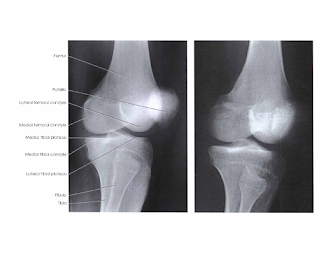

Proyeksi Antero Posterior (AP)

- Kriteria radiograf : struktur yang terlihat distal femur dan proksimal tibia dan fibula terlihat

- ruang femorotibial joint terbuka, dengan articular facets tibia terlihat di akhir dengan visualisasi area permukaan yang minimalis

- tidak ada rotasi dibuktikan dengan tibia condyles dan ruang sendinya simetris

- kira-kira setengah dari pertengahan caput fibula superposisi dengan tibia

- intercondylar eminence terlihat di pertengahan intercondylar fossa

- eksposi yang optimal akan menampakkan garis tepi patella pada distal femur, dan caput fibula dan leher fibula tidak terlihat overeksposi.